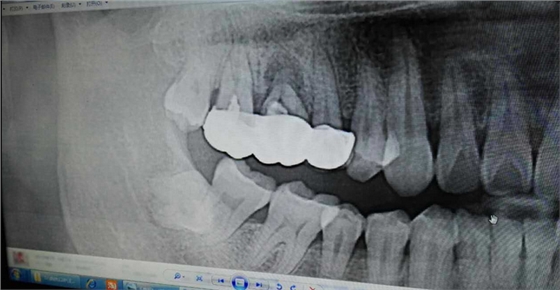

病例:患者男性47歲

右下8骨埋伏并且黏連;從根分叉處通過;有彈性;術(shù)中看到神經(jīng)束

實(shí)在找不到;近中牙冠沒去干凈

像這種不切除的牙冠,以后吸收的可能性不是很大,但有排除的可能性,自己自行排出,要是牙根的話吸收的可能性比較大

像這種沒有癥狀的殘留牙體組織不用去除可以吧